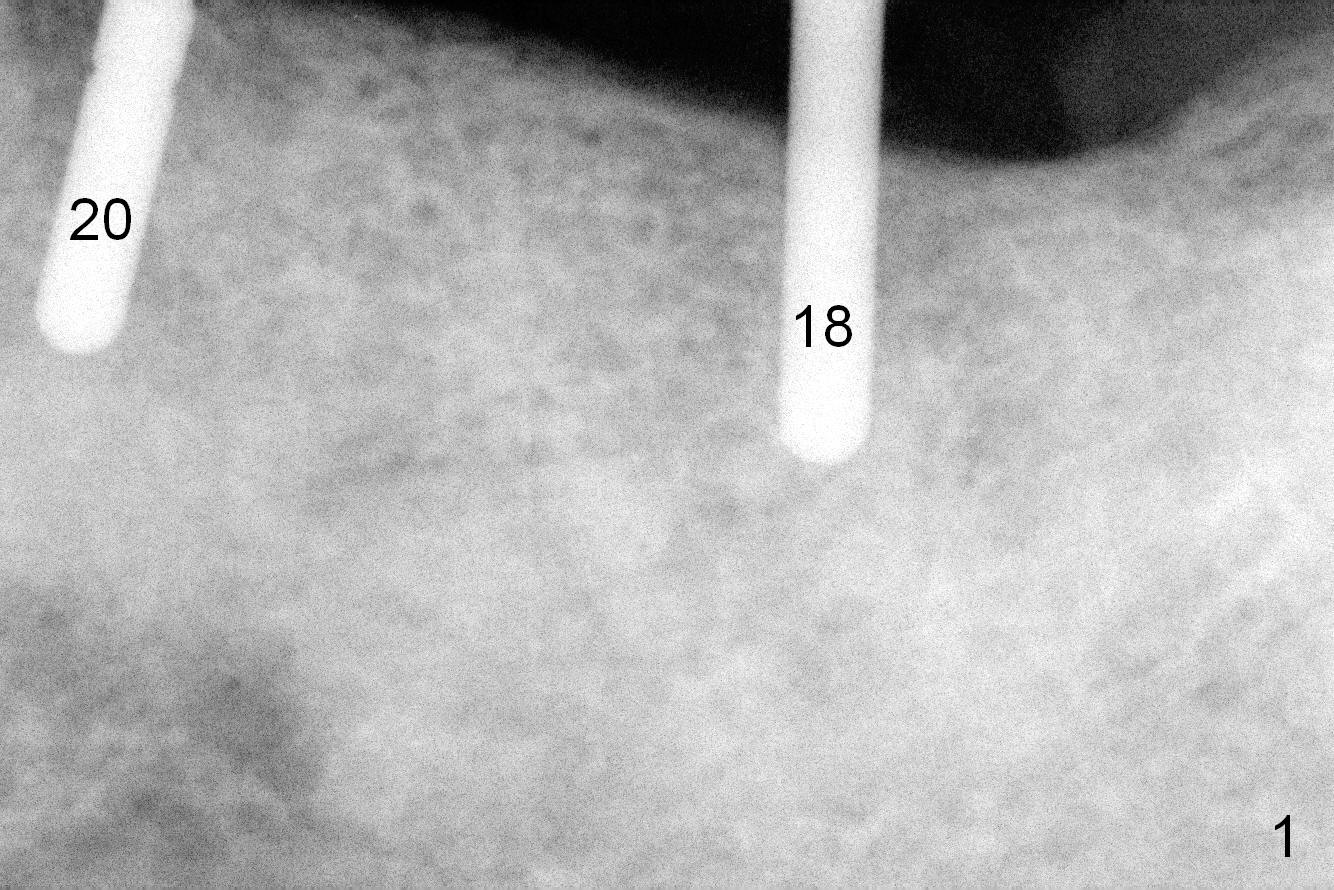

The sites of osteotomies at #18 and 20 are decided by the surgical stent (Fig.1). A 4x14 mm implant is placed at the site of #20 (Fig.2), and a 5x14 mm one at #18 (Fig.3) with primary stability. When 3 mm long abutments are placed for an immediate provisional (Fig.4 A), there is no or limited clearance with the opposing dentition (Fig.5). In spite of the fact that the implants are placed deeper, the abutments and the opposing supraerupted teeth #13 and 15 (Fig.5 arrows) have to be reduced. Finally the abutment at #18 has to be removed. No provisional is fabricated. Periodontal dressing is applied around the abutment at #20 and the adjacent teeth. It appears that the tissue-level implant is not suitable for the 2nd molar with limited vertical clearance.